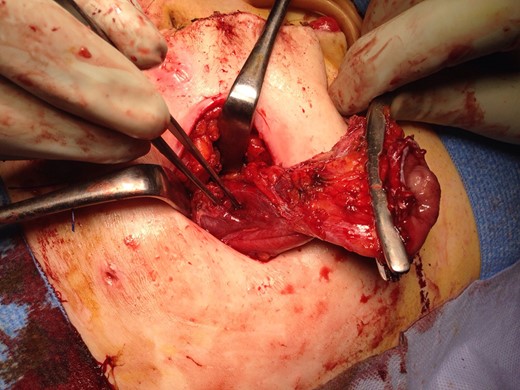

The patient recovered well with the stoma functioning well until Day 6, when she developed a small bowel obstruction. CT scan demonstrated cystic structure compressing the ileum loop within the anterior abdominal loop just before the stoma opening (Figs 1 and 2). Digital stomal examination and Foley’s catheter failed to pass through the stoma opening confirming the obstruction being at the abdominal wall. Failure of supportive measures, the patient was taken to theatre for revision of the stoma. Per stoma endoscopy was attempted with a gastroscope and which also failed to traverse the compression. At surgery, a semicircular skin incision was made adjacent to the stoma revealing what remained of the efferent ileal loop transformed into cystic mass abutting the stoma causing tight compression and was tightly adherent to the afferent ileal loop (Fig. 3). This was drained and partially excised with limited mobilization of the stoma. The remnant mucosa adherent to the afferent ileal loop was cauterized. Her recovery was unremarkable and was discharged Day 4 postsurgery. Histopathology of the partially excised cyst wall confirmed small bowel with viable mucosa showing mucosal flattening and complete loss of the villi.